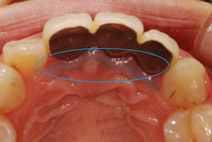

歯を削る量を最小限に抑えるには、治療部分がしっかりと見えなければなりません。

従来までは「肉眼」で見える範囲での治療でしたが、当院では「拡大鏡」や「マイクロスコープ」というものを利用し、肉眼よりも数倍拡大された視野で治療を行っています。

下の画像は肉眼での視野と、拡大鏡の視野の比較となります。

どちらの方が精密な治療ができるかは一目瞭然ですね。